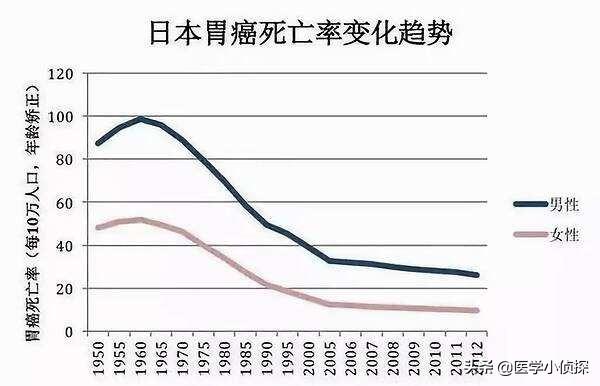

2つ目は、環境と食生活である。皆さんはあまりご存じないかもしれませんが、実は私たちが大学に通っていた頃、先生が当時アメリカに移民した日本人の罹患率に関するデータを見せてくれたんです。初代米国に渡った日本人の胃がん罹患率は約25%低下し、その後、米国に戻るまでに、胃がん罹患率は約25%低下した。第二世代最終的に50%減となった3代目になると、地元のアメリカ人とほとんど同じになる。つまり、この環境要因が胃がんの発生に影響を与えているのだ。